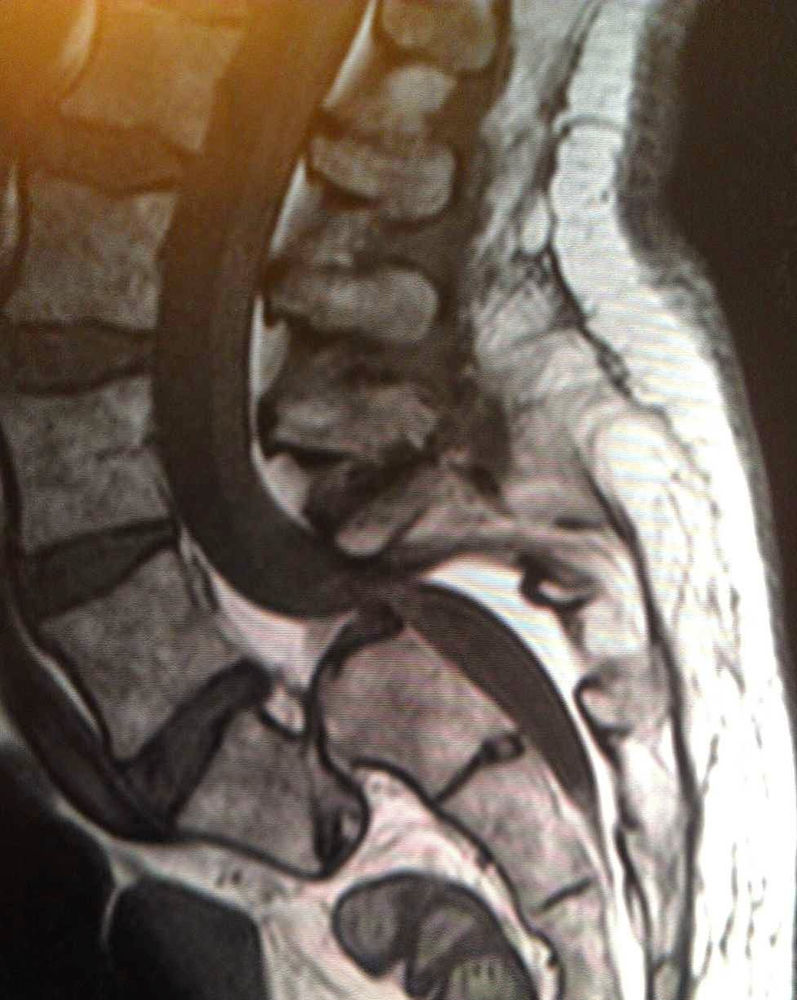

MRI Of Bulging Disc Lower Lumbar What Are Bulging Discs In The Lower Back It is one of the. A herniated disk is a condition that can occur anywhere along the spine, but most often occurs in the lower back. Most bulging discs don’t cause. A bulging disc in your lower back is most often caused by naturally occurring changes as you age. It is sometimes called a bulging, protruding, or ruptured disk. It’s. What Are Bulging Discs In The Lower Back.

Bulging Disc Lumbar Spine MRI What Are Bulging Discs In The Lower Back They are highly prevalent in this area and can lead to. A herniated disk is a condition that can occur anywhere along the spine, but most often occurs in the lower back. Whether it’s a bulging disc in your lower back or a bulging disc. Bulging discs are similar to—but not quite the same as—herniated discs. A bulging disc in. What Are Bulging Discs In The Lower Back.